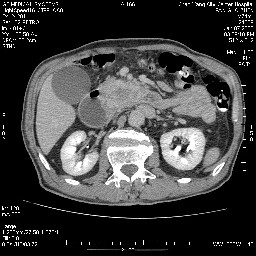

十二指肠水平段腔内占位伴梗阻,中等度较为均匀的强化,洗脱慢,区域淋巴结显示增多,符合腺癌表现。下腔静脉变异。

十二指肠降段扩张,水平段狭窄成鼠尾状,肠壁明显增厚,胰腺勾突增大成不均匀强化,其内可见低密度区,胆囊增大,1十二指肠水平段腺癌侵犯胰腺勾突可能大,2胰腺癌侵犯十二指肠(只有胆囊增大没有肝内外胆管扩张不好解释)代除外.

十二指肠降段扩张,水平段狭窄成鼠尾状,肠壁明显增厚,胰腺勾突增大成不均匀强化,其内可见低密度区,胆囊增大,1十二指肠水平段腺癌侵犯胰腺勾突可能大,2胰腺癌侵犯十二指肠 。